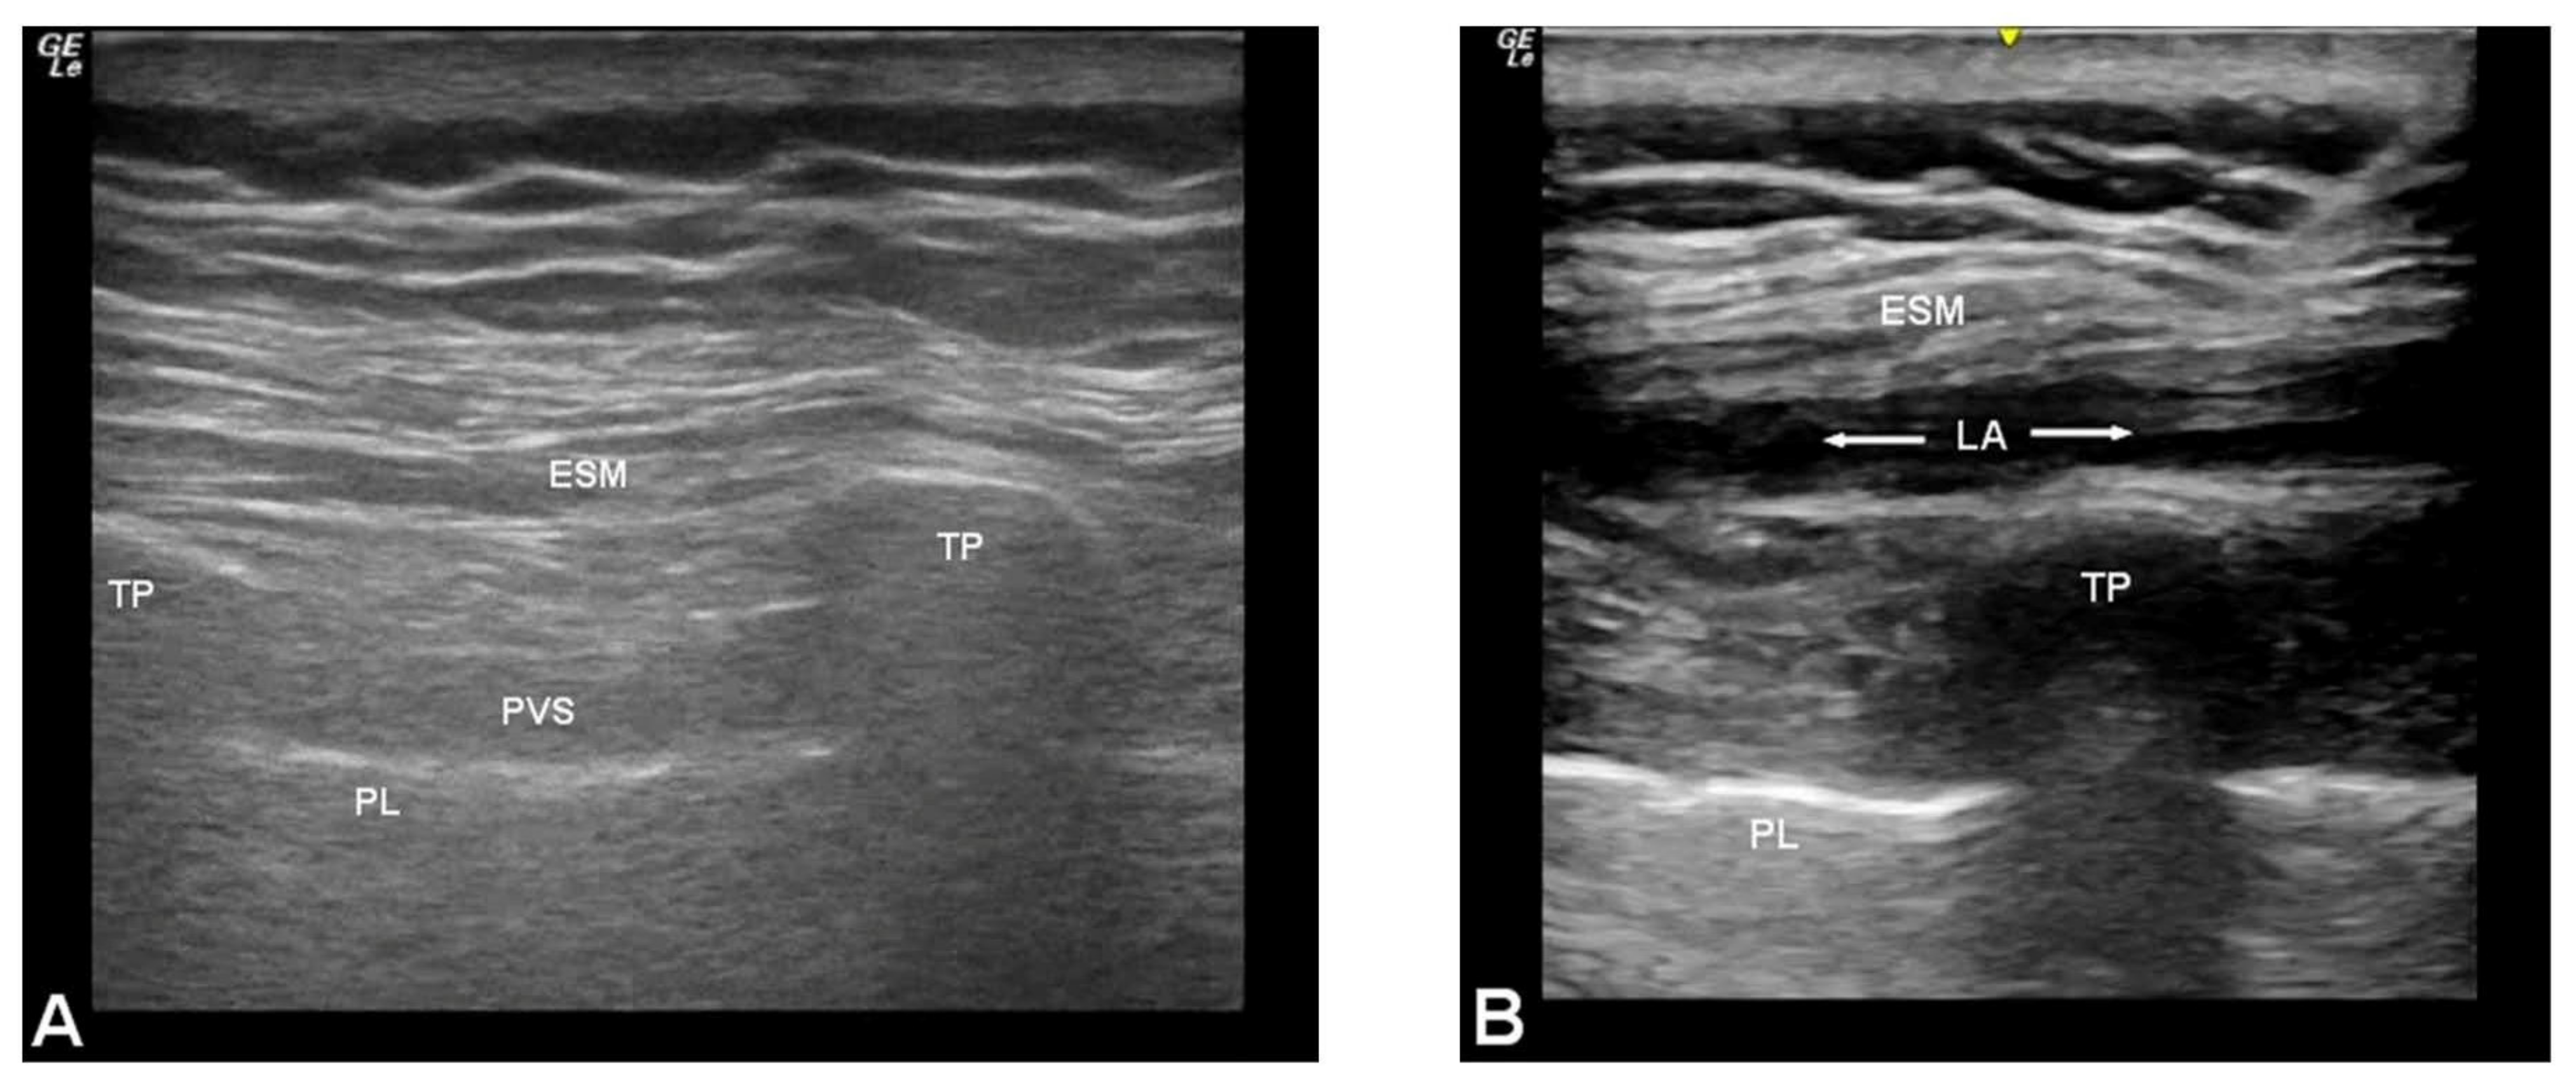

2.3. Technique for Erector Spinae Plane Blocks